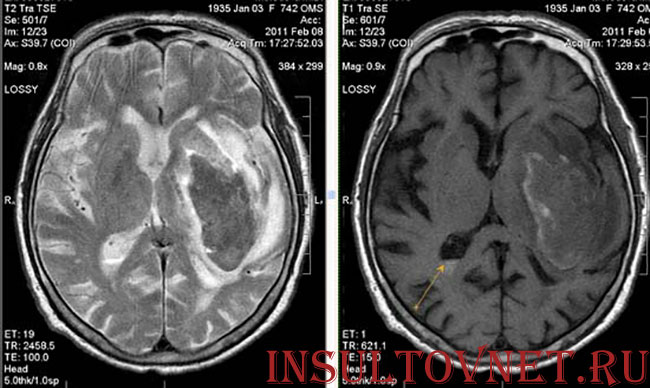

- Магнитно-резонансная томография (МРТ) – альтернатива КТ. Позволяет определить, сколько мозговой ткани вовлечено в процесс, насколько инсульт обширный, с правой или левой стороны головного мозга он локализован, насколько выражен отек, необходима ли операция.